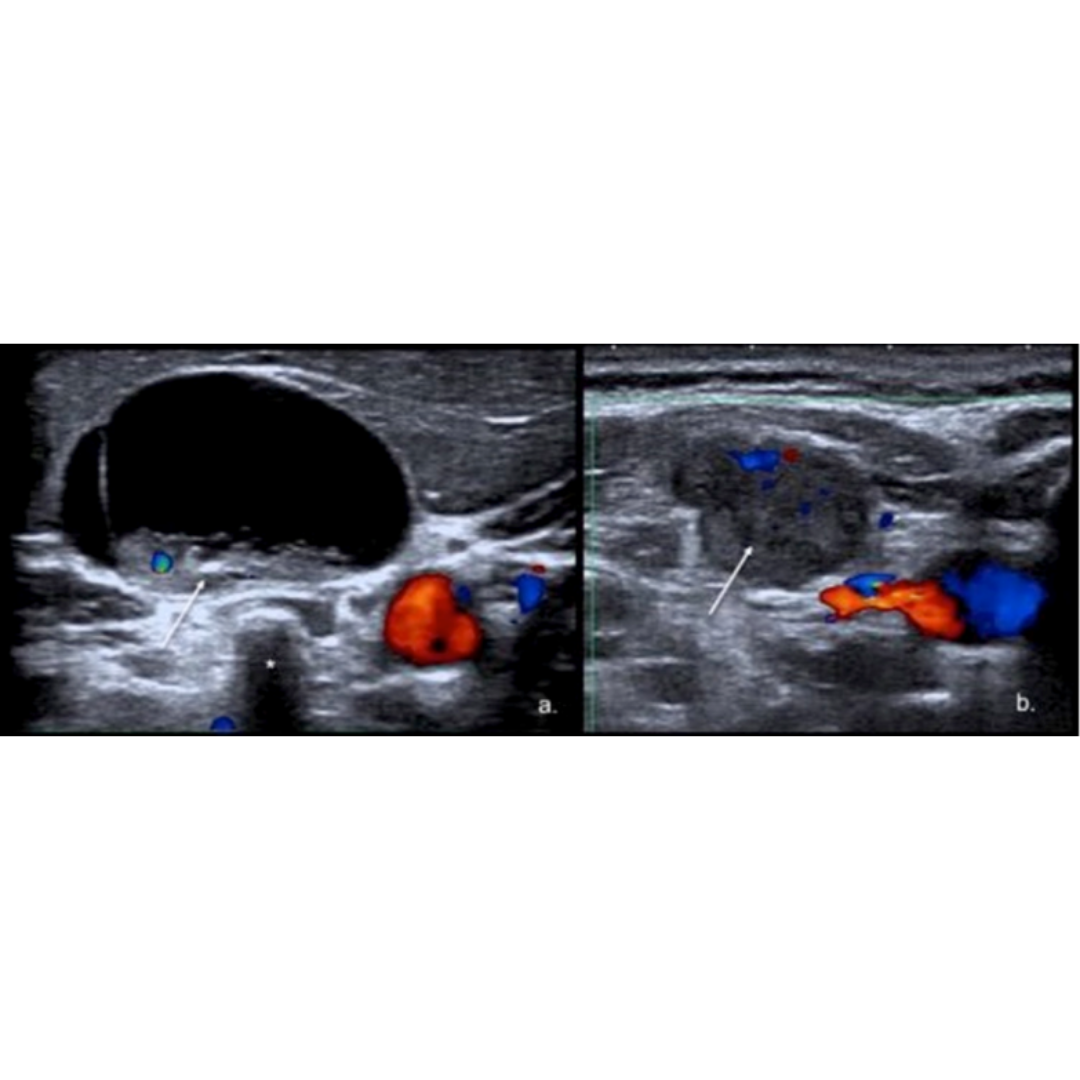

Hematoma

Habitualmente el hematoma postquirúrgico (figura 4) se observa cuando ha existido además de la tiroidectomía, una linfadenectomía en el contexto de un carcinoma de tiroides con metástasis ganglionar. Es un hallazgo que se podría encontrar las primeras semanas posterior a la cirugía.

Hallazgos ecográficos:

Colección con contenido hipoecogénico, de ecogenicidad variable dependiendo el tiempo desde la cirugía será la ecogenicidad, sin vascularización al Doppler color.

Figura 4. Hematoma post quirúrgico, por linfadenectomía izquierda, imagen (a) se observa corte longitudinal y en imagen (b) corte transversal a nivel del segmento cervical III.